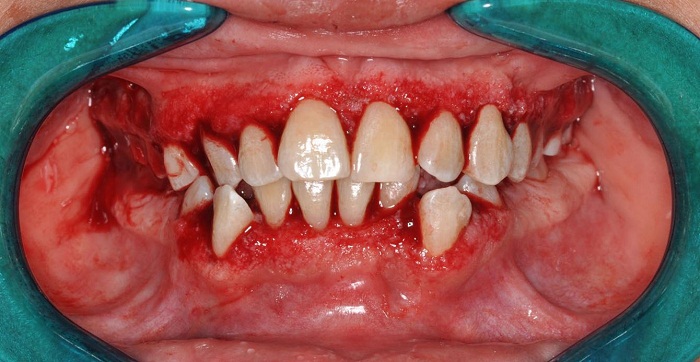

El 29 de abril de 2015, previa sedación con óxido nitroso, se realizó asepsia y antisepsia de la zona. Se aplicó anestesia local con lidocaína al 2 % y epinefrina en una concentración de 1:80.000 mediante técnica infiltrativa, se realizó gingivectomía con bisturí de Kirkland y gingivoplastia con tijeras y electrobisturí (figura 4). Las superficies dentales se limpiaron mediante la técnica de raspaje supra y subgingival ultrasónico/manual y se colocaron placas de acetato 0,16 con cemento quirúrgico en ambos maxilares.

Durante la cirugía, la paciente estuvo con una concentración de 60 % de oxígeno y 40 % de óxido nitroso. Mantuvo una tensión arterial promedio de 169/114 mm Hg. Al finalizar la cirugía, se prescribió 1 g de acetaminofén cada 8 h durante 3 días y enjuagues con 10 ml de clorhexidina al 0,12 % cada 12 h durante 14 días. El tejido gingival del sector anterior inferior se llevó al Servicio de Patología Oral para realizar examen histopatológico.